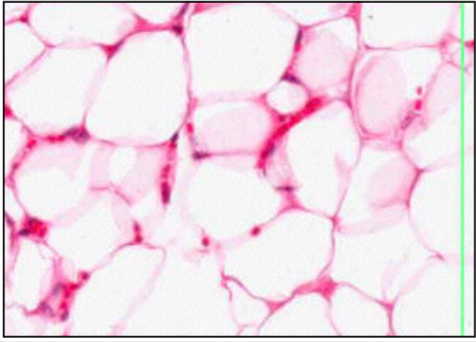

CAPILLARIES

this slide - mature adipose

ENDOTHELIAL CELLS (EM)

- specialised - release vasoactive substances

- capillary @ centre

function:

- active transport of molecules across cytoplasm

- influence muscle tone

- coagulation

- produce cell adhesion molecules - influsence lymphocyte/neutrophil migration